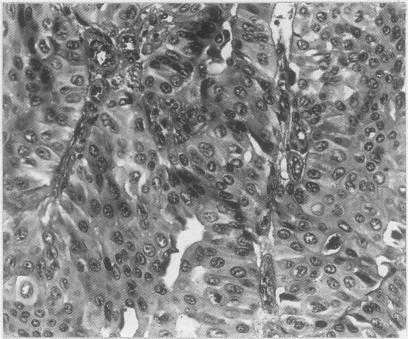

The factors regulating the expression of the Lewis blood group related antigens in tissues have yet to be clarified. In an attempt to resolve some of the existing controversies the quantitative interrelationship of the Le(a), Le(b), X and Y antigens in normal urothelium and transitional cell carcinomas (TCC) was studied using biopsy specimens derived from 22 patients whose ABO and Lewis red blood cell phenotype was known. A quantitative scale was devised to encompass both the extent and intensity of the immunohistochemical reactivity in one numerical value (score). The expression of these four antigens in the normal urothelium followed a characteristic pattern that is related to but not identical with the red blood cell phenotype. An excess of Le(b) and Y in the urothelium correlated with the Le(a-b+) red blood cell phenotype, while a relative increase in Le(a) and X (at the expense of Le(b) and Y) was associated with the Le(a+b-) red blood cell phenotype. This pattern can be accounted for by the combined effects of differential gene expression and substrate availability. The quantitative comparison of the antigenic make-up of TCCs with the corresponding normal tissue phenotype shows consistent trends, suggesting that the changes associated with neoplasia derive primarily from the suppression of specific gene products and, secondarily, from altered competitive substrate utilisation.